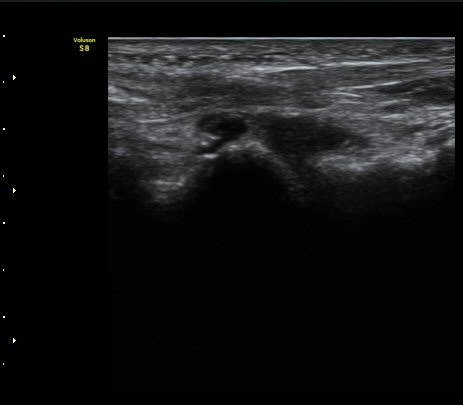

Àδë Á¾°ñºÎÂøºÎ Á¾´Ü¸é°Ë»ç¿Í Ⱦ´Ü¸é°Ë»ç¿¡¼­ Á¾°ñÀÇ °ß¿­°ñÀýÀÌ °üÂ÷µÊ(»çÁø 4, 5).